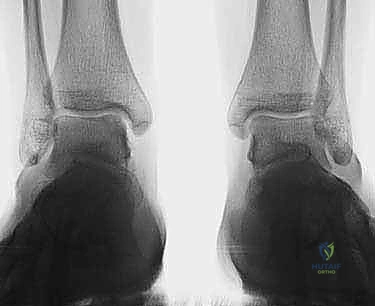

- الأشعة السينية (X-rays): تُستخدم كخطوة أولى لاستبعاد الكسور العظمية الكبيرة والتهاب المفاصل المتقدم. في بعض الأحيان، يمكن رؤية "ظل" أو كيس عظمي يشير إلى وجود آفة.

- التصوير بالرنين المغناطيسي (MRI): هو المعيار الذهبي (Gold Standard) لتشخيص OLTs. يُظهر الرنين المغناطيسي الغضروف بدقة عالية، ويحدد حجم الآفة، عمقها، وحالة العظم تحت الغضروفي (مثل وجود وذمة عظمية - Bone Marrow Edema).

- الأشعة المقطعية (CT Scan): يطلبها الدكتور هطيف أحياناً للحصول على خريطة ثلاثية الأبعاد دقيقة للعظم، مما يساعد في التخطيط الجراحي وتحديد حجم الرقعة العظمية المطلوبة للزرع.